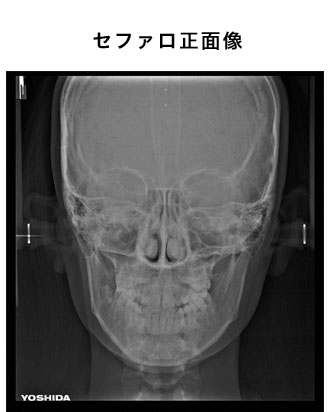

デジタルレントゲン

当院ではあえてCTを採用せず、デジタルパノラマ・セファロレントゲンを採用しました。

CTの1回あたりの撮影の際の被爆量は250μSであるのに対し、デジタルパノラマ・セファロレントゲンは10分の1の25μSvであるからです。

(デジタルパノラマ・デンタルレントゲンは10μS)

被爆量の低減について、医療側の努力が必要であるからです。

3次元的なレントゲンの検査方法として、下記の様な物があります。

方向の異なる画像を読影して診断する事が可能です。